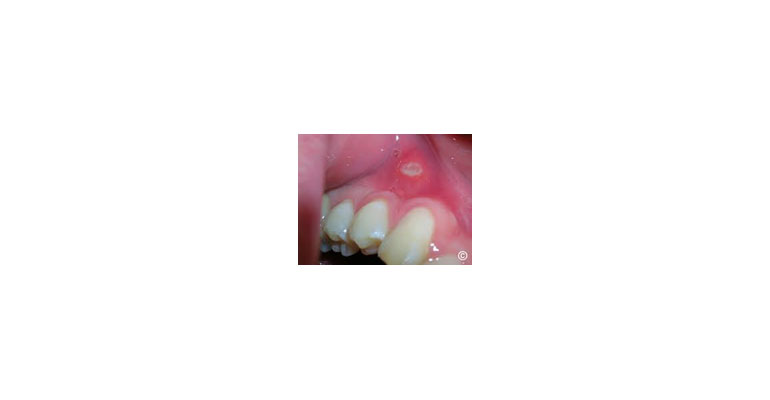

A case done by me to show it can be cured- earlier the better!

Canker Sores (Aphthous Ulcers):These are small, painful sores that typically appear on the inside of the lips, cheeks, or on the tongue. They are usually white or yellow with a red border and can be recurrent. The exact cause is not well understood but may be related to stress, dietary factors, or immune system issues.

Oral lesions, also known as mouth sores or stomatological conditions, refer to any abnormal or painful changes that occur within the oral cavity, including the lips, gums, tongue, palate, and the inside of the cheeks. These lesions can be caused by various factors, including infections, injuries, systemic diseases, or other underlying conditions. Understanding the different types, causes, symptoms, and treatments for oral lesions is essential for maintaining good oral health.